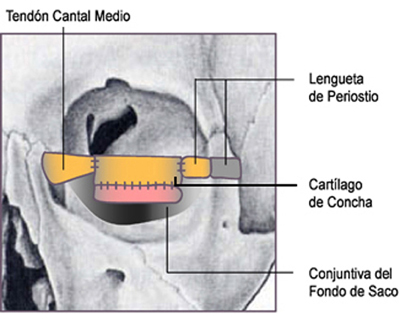

Ante la ausencia total del parpado inferior izquierdo y de un área de 1.2 cm. de piel en el canto externo , secundaria a la resección en la cirugía de Mohs, pensamos primero en darle estructuras básicas de soporte al nuevo parpado, para lo cual tomamos como puntos básicos de anclaje, el tendón cantal medio del lado nasal, y un colgado de periostio en forma de lengüeta, del reborde orbitario temporal , a nivel del tubérculo de Wihtnal.

Procedimos entonces a la toma de un injerto de concha auricular de 3 cm. de largo por 1.5cm. de ancho en forma de media luna, mas ancho en el centro que en los extremos, entrando por una incisión en piel retroauricular, que se cerro luego con una sutura continua de seda Negra 4-00.

El injerto de cartílago auricular, naturalmente curvo, se ancló a estos dos soportes básicos nasal y temporal con puntos separados de Dacrón 6-00.

La conjuntiva del fondo de saco se suturó al borde inferior del injerto de cartílago con puntos separados de Vicryl 6-00. El músculo orbicular y los retractores del parpado inferior se anclaron a la región media del injerto de cartílago. (Figura 15)

En la región cantal lateral, la piel restante de la mejilla se ascendió como si se tratase de un colgajo y se ancló al periostio del reborde orbitario lateral, suturando luego por planos, para llenar la carencia de tejido en esta área, lo cual redujo en general el lecho quirúrgico.

Figura 15 Elementos estructurales del nuevo párpado inferior